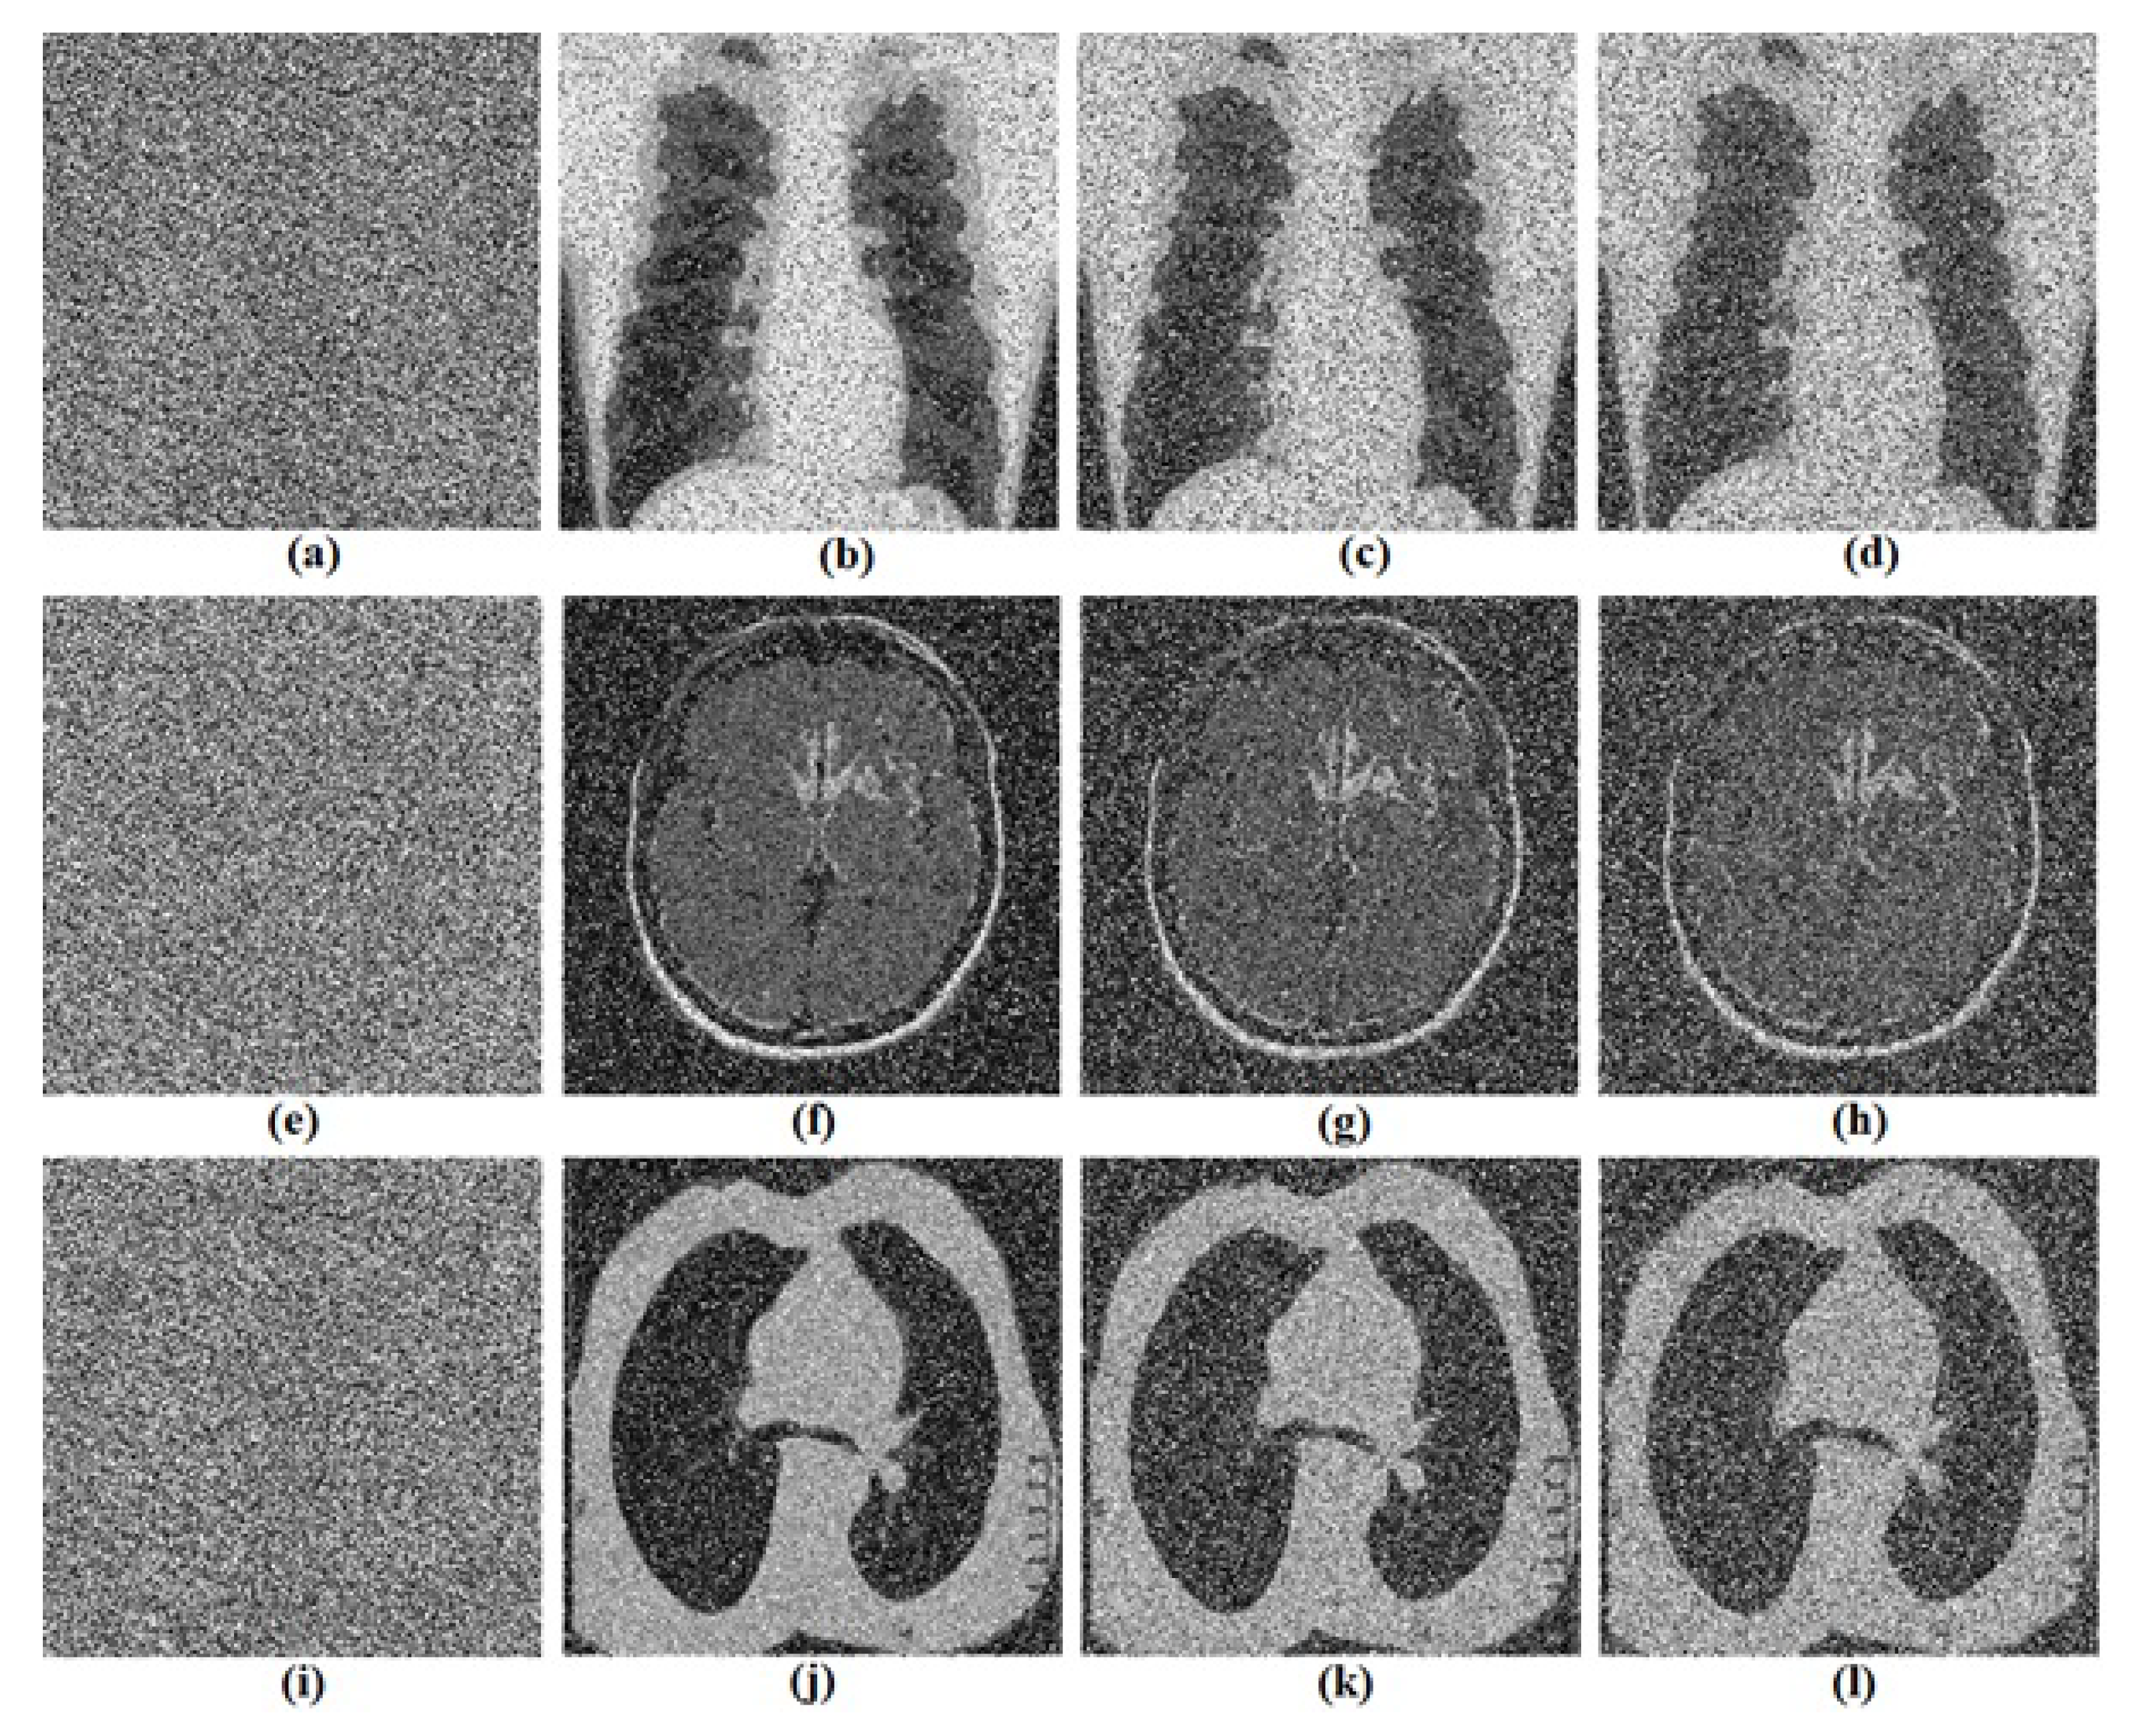

5.2. Computational Results

5.3.4. Noise Attacks